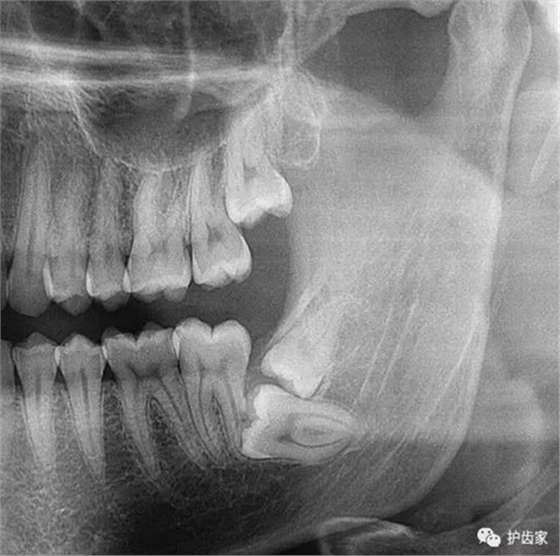

拍片也為了了解下頜神經與智齒的關系,一般離得近,有醫(yī)療風險的,基本沒有醫(yī)生愿意拔,現(xiàn)在沒人為了幾百元,賠上自己的職業(yè)生涯。誰都怕拔智齒,敲打智齒,一不小心,碰到神經,就攤上大事了。有理都說不清。

通過拍片可以了解牙齒本身:生長方向,牙根數目,牙根是否彎曲,膨大等。

與重要解剖結構的位置關系:如上頜磨牙與上頜竇的關系;下頜磨牙與下頜神經管的關系;兒童在混合牙列期恒牙與乳牙胚的關系等??梢詼p少拔牙的風險。

拔智齒必須拍片,一方面是看智齒的位置及方向,為拔智齒制定拔牙方案。另一方面,了解智齒周圍情況,了解下頜神經位置,規(guī)避醫(yī)療風險。當個醫(yī)生還得前怕狼后怕虎的,大家多體諒牙醫(yī)!